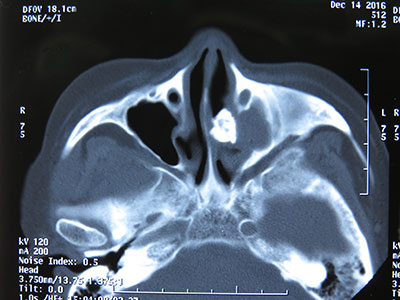

图二:鼻窦CT 所示

患者,女性,64岁,主诉左侧鼻腔涕中带血2-3月,伴左侧鼻塞不适,嗅觉可,偶尔头痛,无面部麻木、压痛、张口受限等症,饮食及睡眠正常,大小便正常,体重无明显变化。体格检查:一般情况好,鼻外形正常,鼻中隔略右偏,鼻腔粘膜干燥暗红,左侧中鼻道可见大量血痂,触之易出血,中鼻道具体结构无法窥清。鼻窦CT示:左侧中鼻道可见异常密度增高影,形态不规则(图1、2)。患者入院后在全麻下实施了鼻内镜下左侧鼻石取出术。术中见左侧鼻腔中鼻道一直径约1.5cm大小形态不规则的黑色鼻腔异物(图3),硬如石块,轻柔取出,中鼻道粘膜充血糜烂伴肉芽组织增生,取部分肉芽组织送病理,开放并扩大左侧上颌窦口。术毕左侧鼻腔填塞可吸收性纳吸绵及止血纱布,手术过程顺利。术后予抗炎消肿治疗,患者恢复平稳,顺利出院。术后1月电话随访患者无左侧鼻腔出血及头痛不适,鼻通气顺畅,感觉良好。病理回报慢性炎症。

讨论:鼻石,也叫鼻石病或鼻石症,是矿物盐类在鼻腔异物周围经数年的沉积而形成的块状物。鼻石是一种鼻腔少见病,多发生于一侧鼻腔,病程可长达数年。有学者认为在鼻腔异物的基础上,炎性渗出物包裹异物、鼻腔分泌物分解出多种无机盐沉积而逐渐形成,其成分主要为磷酸钙、氯化钠等。鼻石分为真性和假性,以后者多见。以外源性异物为核心称假性鼻石,包括纽扣、纸团、石块、水果核、豌豆、寄生虫、木棒、玻璃、纱布等;以内源性物质为核心称真性鼻石,包括细菌、干痂、坏死上皮、凝血块、碎骨片、牙齿等。典型的鼻石诊断主要靠鼻内镜检查,鼻窦CT检查可提高本病的确诊率。本例在CT表现为均匀致密的高密度影,与鼻腔粘膜形成鲜明对比,鼻石应与鼻异物及鼻腔牙相鉴别,前者有明确的异物塞入鼻腔病史,一般病程短,与周围组织无联系;后者为鼻底部白色突起的硬物,不易推动,X线片示高密度影,其根在鼻部骨质内。鼻石的治疗建议在鼻内镜下取出,一般预后良好,小的鼻石可在门诊局麻取出,较大较多的鼻石建议全麻下取出。本例鼻石较大,采取全麻取出,视野好,术中损伤小,患者无痛苦。